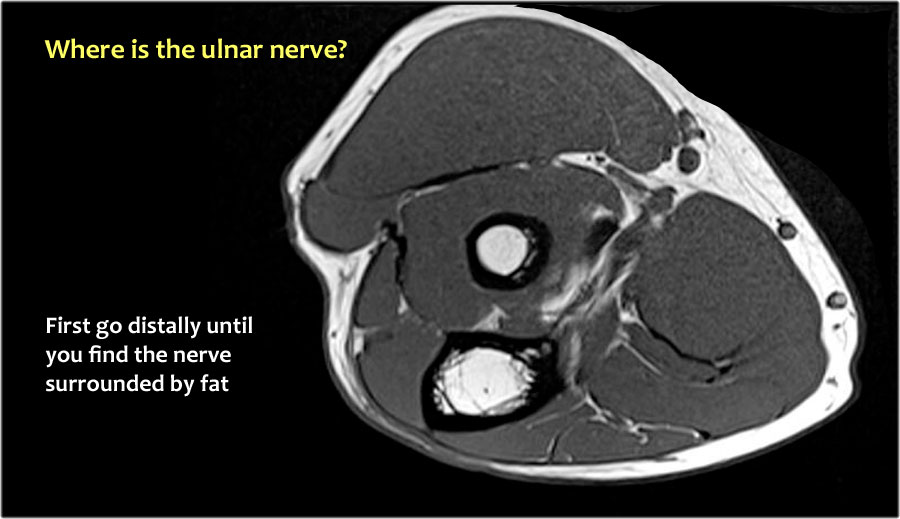

Vì vậy, khi chúng ta quay lại hình ảnh, bạn sẽ nhận thấy rằng có thể khó tìm thấy dây thần kinh.

Bất kỳ cấu trúc dưới da nào trong số này đều có thể là dây thần kinh đã được chuyển vị.

Một cách để thực hiện là đi theo các cấu trúc về phía xa cho đến khi tìm thấy dây thần kinh trụ ở phía xa tại vị trí bình thường của nó ở vùng cẳng tay gần được bao quanh bởi mô mỡ.

Sau đó khi bạn theo dõi nó về phía gần, bạn sẽ nhận thấy rằng đây là một trường hợp chuyển vị dưới da.